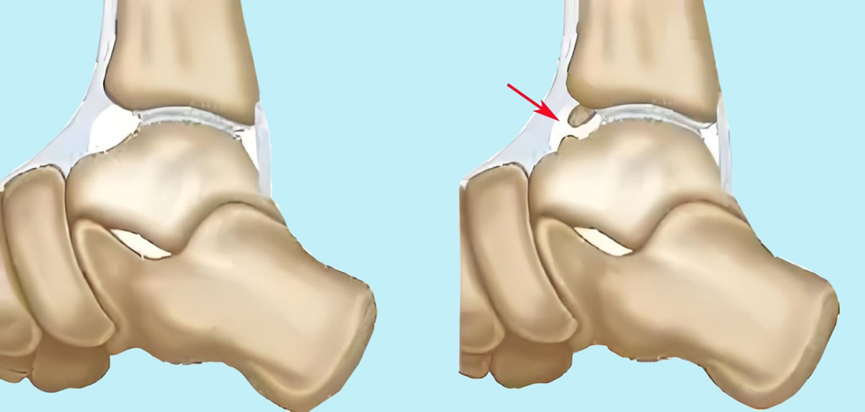

图3:胫骨下唇与距骨颈部重复撞击,形成骨赘

图4:踝前撞击综合征的X线表现

▶踝关节过度跖屈,造成踝关节前关节囊反复被牵拉,胫骨下唇与距骨颈部重复撞击,形成骨赘或关节游离体。